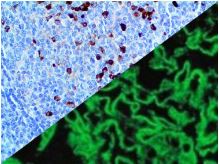

Bio SB has developed a highly sensitive Immunofluorescence and non-biotin monovalent Fab micropolymer IHC detection systems for the detection of IVD antibodies for Complement (C1q, C3c, C3d, C4c, C4d), Serum Proteins (Albumin and Fibrinogen) and Immunoglobulins (IgA, IgD, IgE, IgG, IgM, Kappa and Lambda) related to autoimmune conditions. Our innovative IF and IHC detection systems and high affinity antibodies, have opened the doors for a faster and accurate Immunofluorescence and Immunohistochemistry applicable to Autoimmune Disease like Nephropathies and Lupus.

These antibodies and detection systems are intended for use in Immunohistochemical (IHC) and Immunofluorescence (IF) applications of formalin-fixed paraffin-embedded tissues (FFPE), frozen tissue sections and cell preparations.

InDirect Immunofluorescence Detection

Rabbit FluoroDetector FITC |

Rabbit FluoroDetector FITC with FluoroMounter |

Rabbit FluoroDetector FITC with FluoroMounter with DAPI |